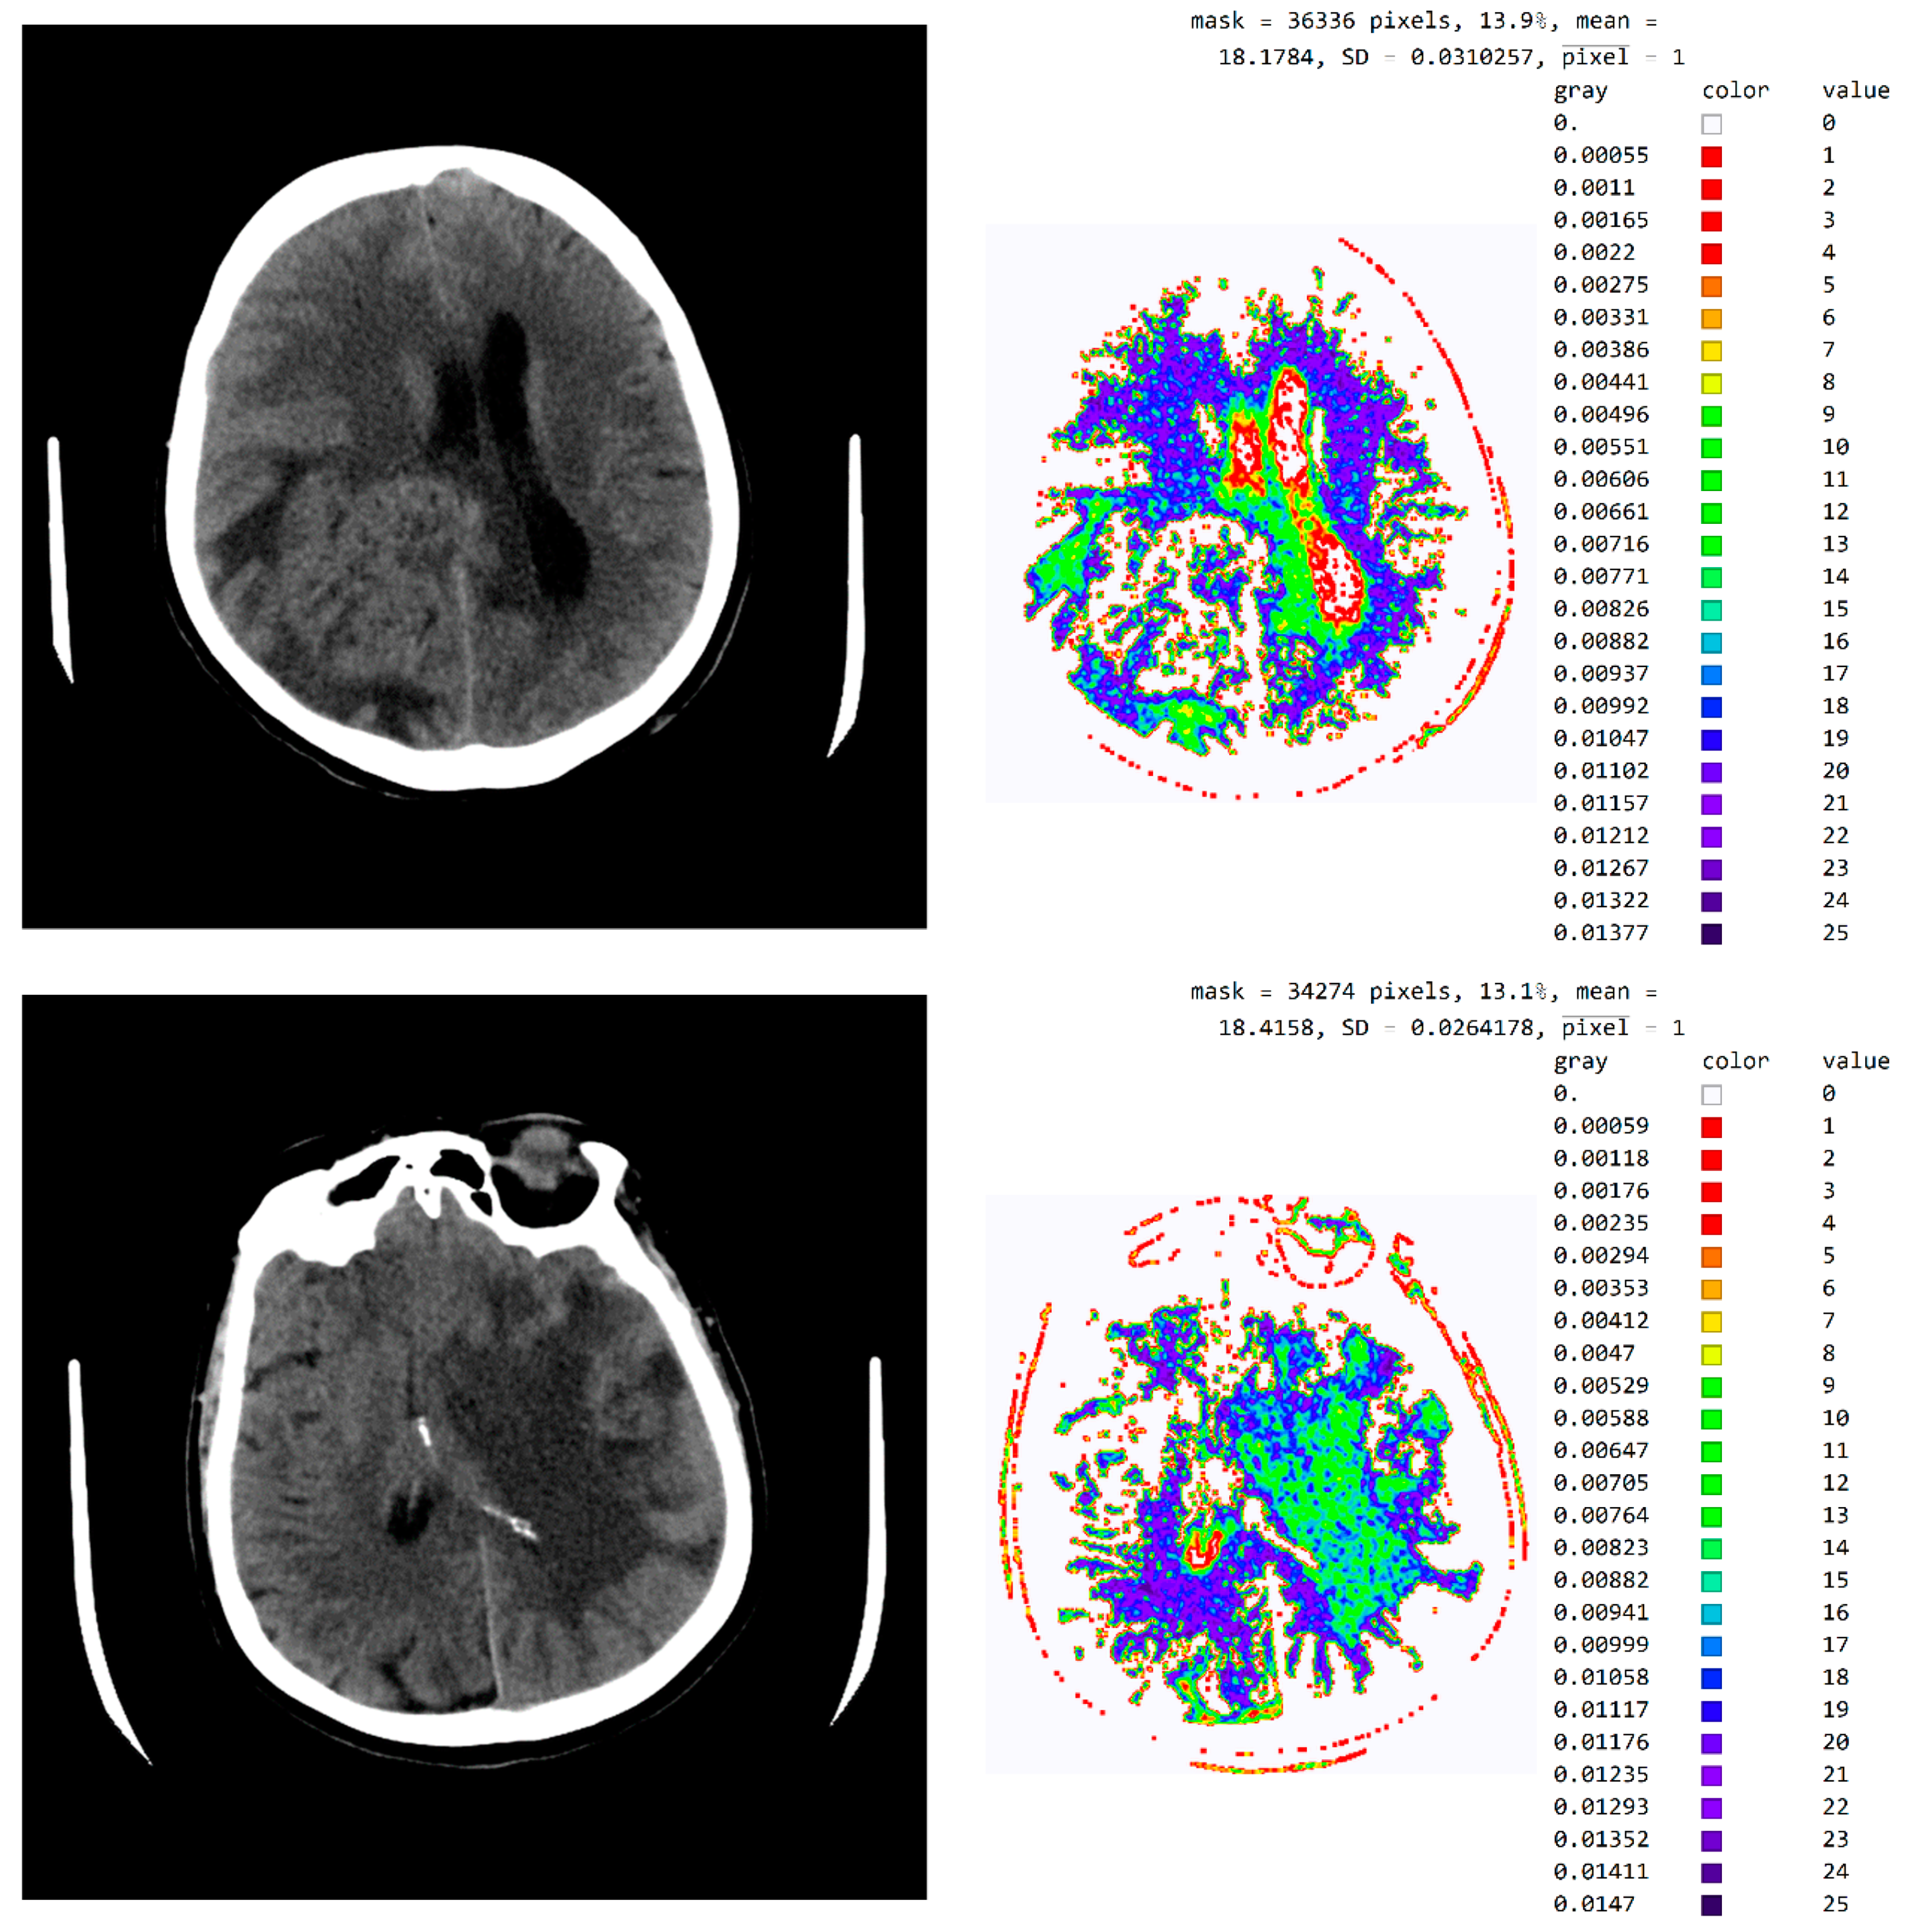

2.2. Smart Visualization Method (SVMI)

3.1. Technological Description